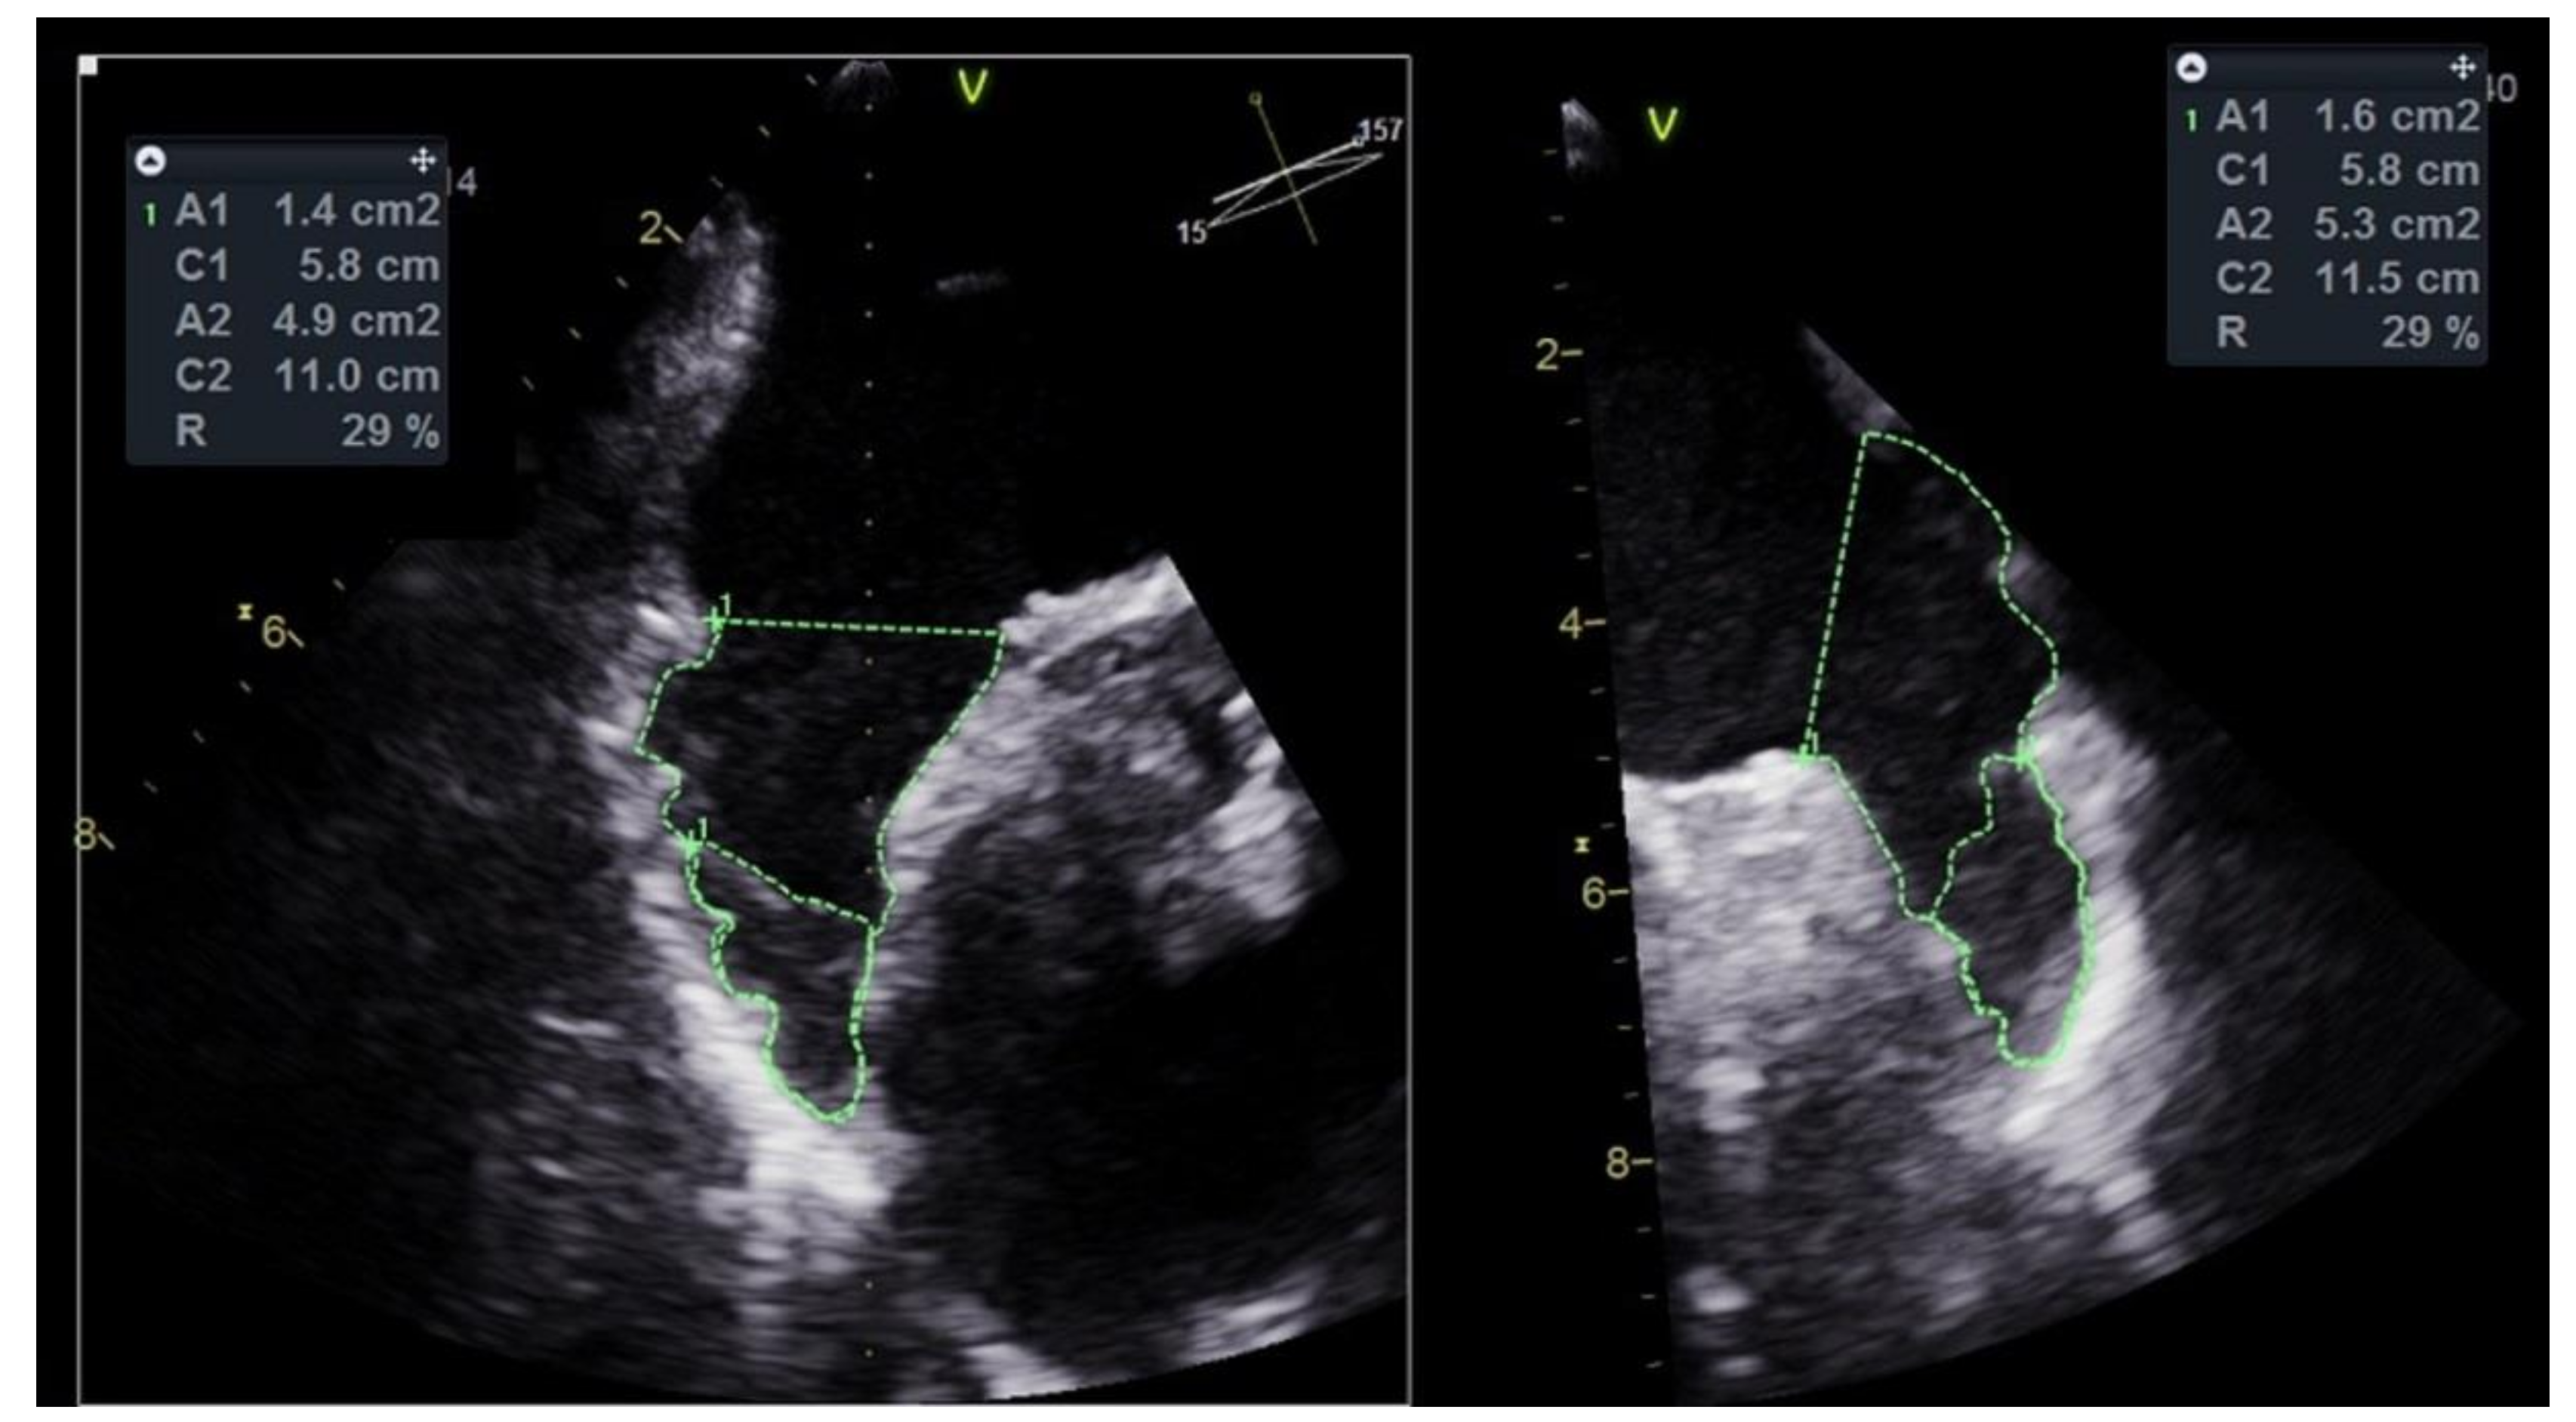

Patients had TEE performed just before and during the PLAAC procedure, in which the thrombus was visualized in multiple views. Thrombus position in LAA was described as located in a proximal or distal portion of LAA. Additionally, the mean percentage of LAA volume covered by thrombus was approximated with a calculation of mean percentage of area covered by LAAT to the LAA area obtained from two TEE projections—30°–60° and 120°–150° (Figure 1). Anatomical characteristics of LAA included: (1) classification to one of four LAA shape variants (chicken wing, windsock, cauliflower and cactus); (2) measurement of the longest (D1) and shortest (D2) diameters of the LAA orifice in the landing-zone position; (3) measurement of LAA depth; and (4) calculation of the orifice eccentricity index (EI) according to an equation: EI = 1 − D2/D1 [11].

Figure 1.

Measurement of percentage of left atrial appendage volume occupied by thrombus in transesophageal echocardiography (TEE) (Supplementary Video S1). A1 and A2, Areas 1 and 2; C1 and C2, Circumferences 1 and 2; R, ratio A1/A2.